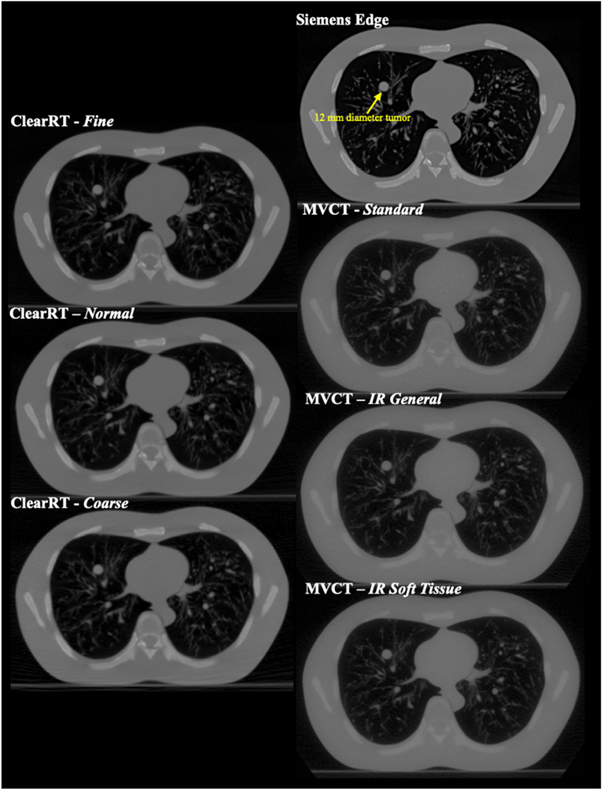

Dose distributions were calculated for images acquired of the N1 ('LUNGMAN') multipurpose chest phantom (Kyoto Kagaku Corporation, Ltd,. Kyoto, Japan). The phantom includes a main body (chest wall with a girth of ∼100 cm), mediastinum (heart and trachea), pulmonary vessels and bronchus, and a diaphragm. The vessels and soft tissue structures are constructed with polyurethane, while synthetic bones are composed of epoxy resin and calcium carbonate. The substitute materials are designed to have x-ray absorption rates close to those of human tissues, while the chest cavity is designed to simulate realistic scatter conditions. Simulated tumors (urethane foam) of various diameters are also included and can be placed anywhere within the thoracic cavity. In this study, a spherical tumor 12 mm in diameter was placed in the right lung for the small volume plan. Thorax phantom images were acquired with the ClearRT system for Thorax anatomy, X-Large body size, 440 mm FOV, and Fine, Normal, and Coarse mode protocols (note that despite Coarse mode images of the calibration phantom displaying noticeable artifacts as discussed previously, Coarse mode images of the thorax phantom were of sufficient quality for use in this study). Acquisitions with the MVCT system were performed with Fine mode and a 1 mm reconstruction interval for each reconstruction algorithm. The thorax phantom image for the planning CT system was acquired with a high mAs chest protocol at 120 kVp with an FOV of 400 mm. Axial image slices of the thorax phantom for each of the acquisitions described is displayed in figure 2.

Figure 2. Axial image slices of the anthropomorphic thorax phantom for each of the imaging systems evaluated in the study. The 12 mm diameter spherical tumor is labeled and visible in the right lung.